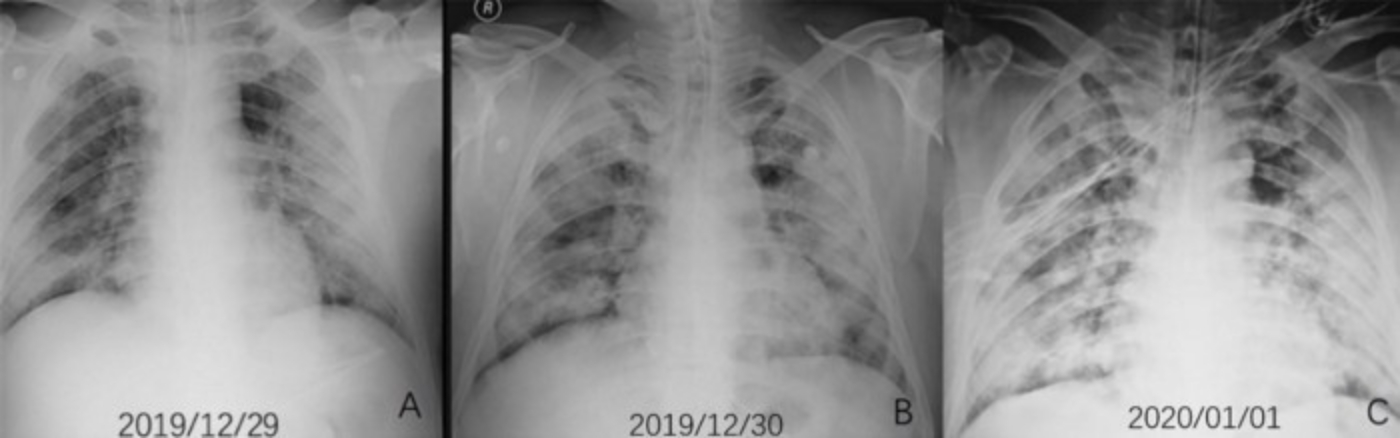

他指出,這次疫情在國外重症的患者身上有發現到出現急性呼吸窘迫症(Acute respiratory distress symdrome,簡稱ARDS),「這表示肺部充滿了很多液體,而且肺部X光的表現很值得注意:整個肺部基本上都是白的。」他提到,ARDS的患者非常難維持氧氣,且ARDS的死亡率也很高、約4成,治療方法正是使用呼吸器,透過外部的壓力將氧氣和血液進行氣體交換。